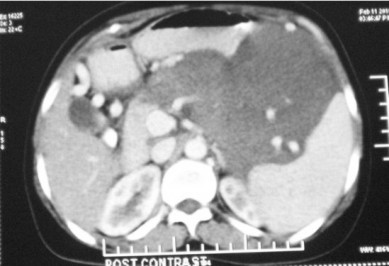

A 35-year-old female presented with dull aching pain and lump in central abdomen gradually increasing in size for last two years. Patient had no history of vomiting, fever, jaundice, anorexia and weight loss. There was no history suggestive of previous episode of acute pancreatitis. On abdominal examination, a 13x16 cm nontender, firm, retroperitoneal lump was palpable in the epigastrium, left hypochondrium and umbilical region along with splenomegaly. CECT of the abdomen demonstrated well defined 15x15 cm solid mass arising from body and tail of pancreas with splenomegaly (Figure 1). Splenic vessels were encased by the mass. The head of the pancreas was normal. The mass was free from stomach and it was not involving the superior mesenteric vessels. There was no lymphadenopathy or free fluid. With a suspicion of benign tumor of the pancreas patient was planned for distal pancreatectomy with splenectomy. Intra-operatively there was a 15x15 cm firm mass was found to be arising from the body and tail of the pancreas (Figure 2). The mass was completely resected by performing distal pancreatectomy and splenectomy. Postoperative period of the patient was uneventful and she was discharged on postoperative day nine.

Figure 1. CECT abdomen showing solid mass arising from body and tail of pancreas. |